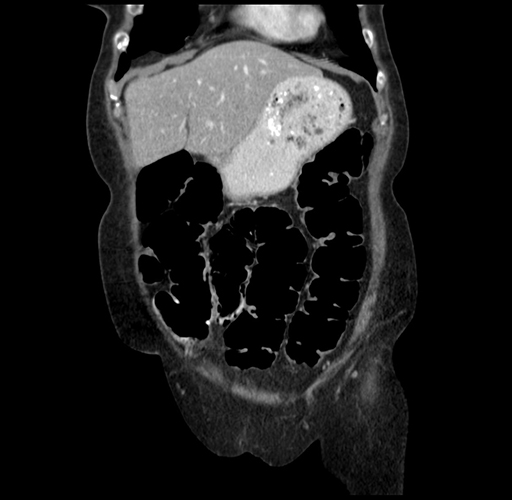

Pre-Chemo: Coronal Venous

Coronal Venous